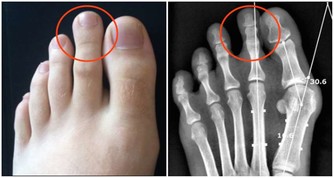

很多人發現,夏天的時候皮膚很容易過敏,皮膚很容易瘙癢,撓了之後,身上、手上就會起一些小水泡,這種小水泡就是汗皰疹,是因為出汗不良,身體毒素過多引起的。小水泡的出現其實是一種身體的自我保護機制的體現,它在用這種方式提示你該排毒了。